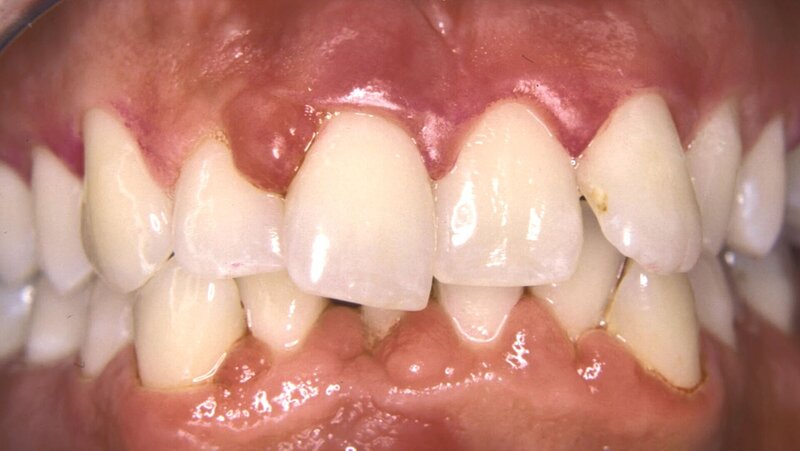

Der Falltyp 2 der Stadium-IV-Parodontitis beschreibt den Patienten mit pathologischen Zahnwanderungen, gekennzeichnet durch Zahnelongationen, -lückenbildungen und -auffächerungen, die für eine kieferorthopädische Korrektur geeignet sind. Die betroffenen Zähne weisen zumeist stark fortgeschrittene Attachmentverluste und Entzündungszeichen auf (Abbildung 1).